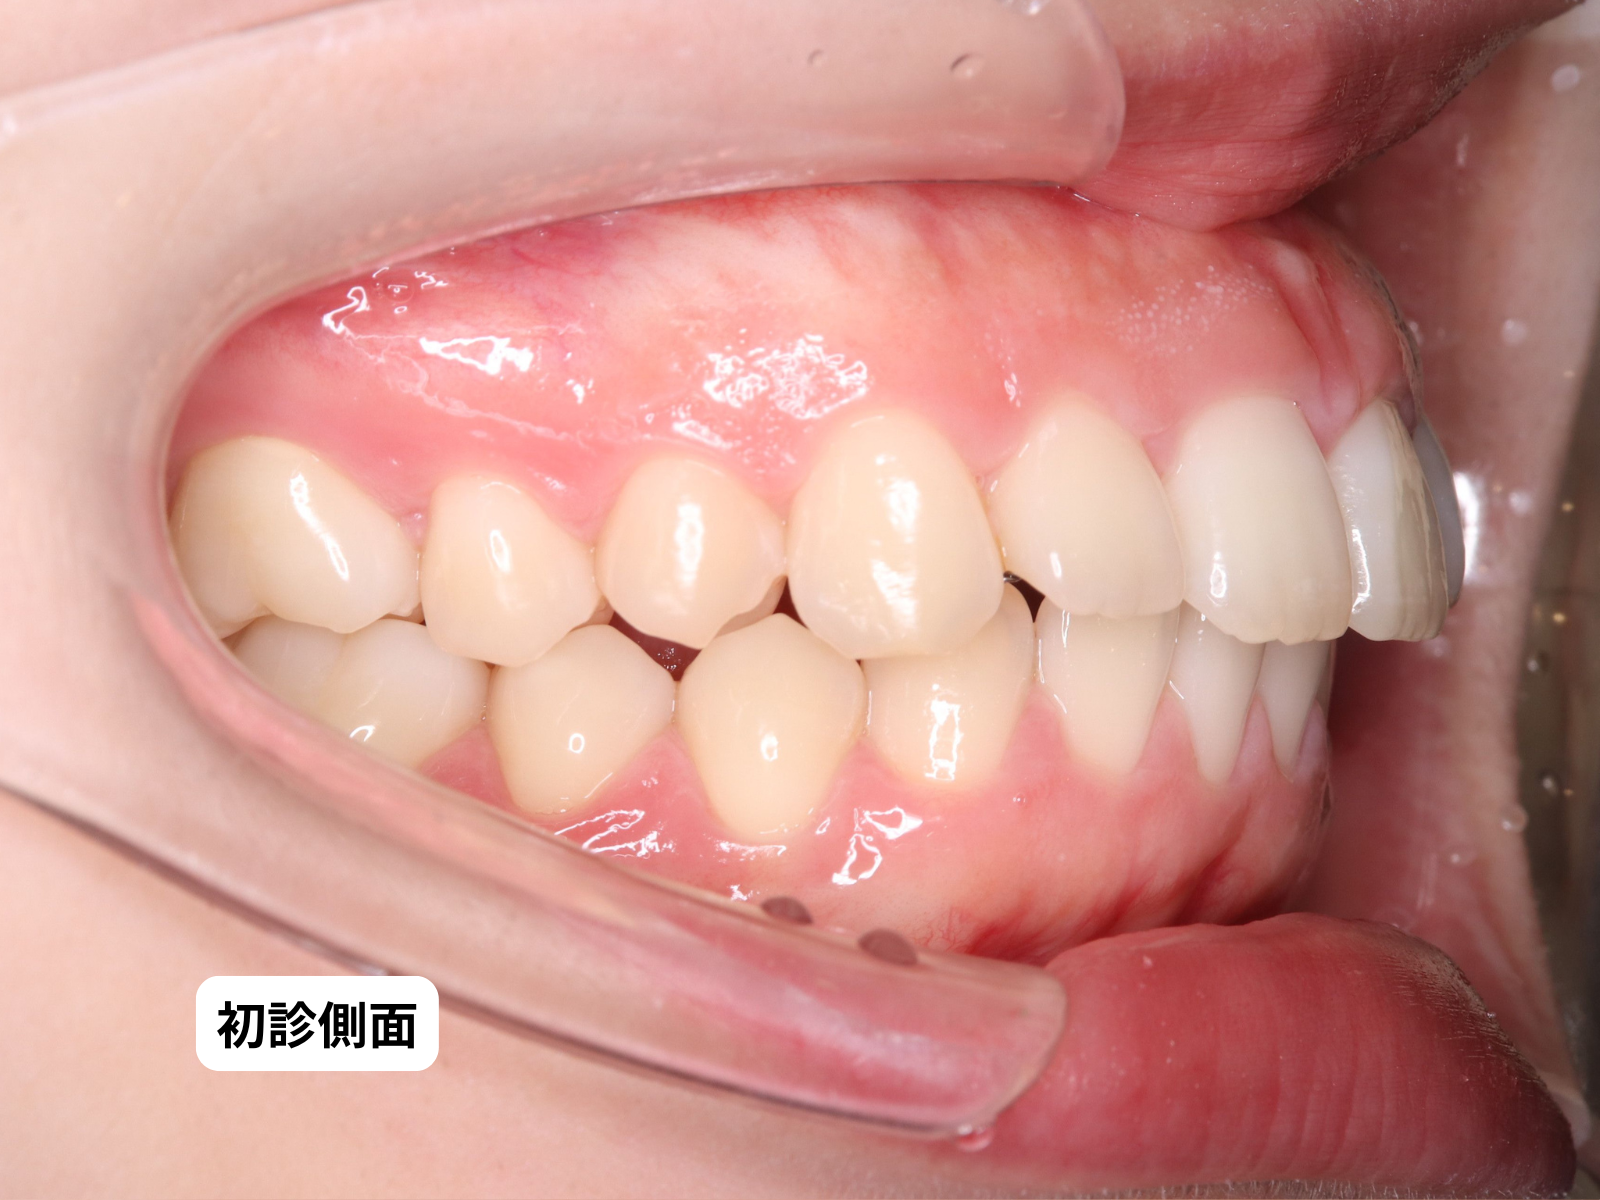

初診時の側貌(79-02)|奈良の矯正歯科

Before 初診時側貌 Before(79-BA1a)|奈良の矯正歯科

側貌——Eラインを基準とした口元の位置の変化。